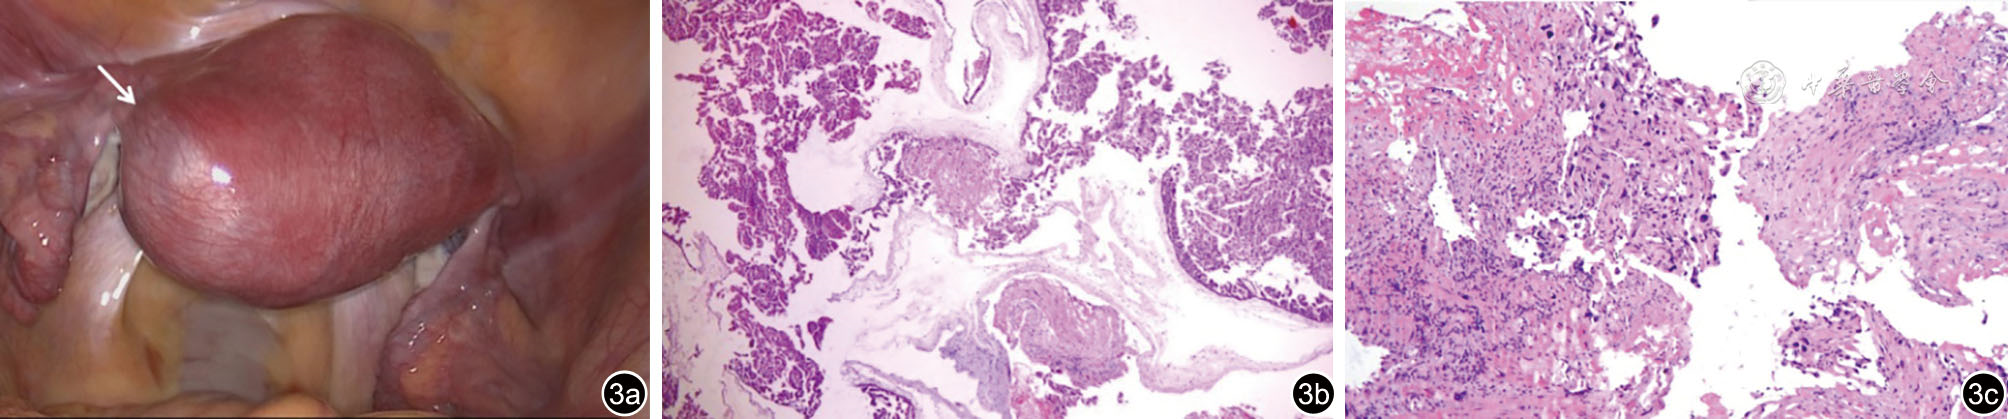

图1 肌壁间异位葡萄胎妊娠经阴道超声图像。图a、b示宫底略偏左肌层内见不均质回声区,内部见不规则无回声区及多个囊泡状无回声(箭头);图c、d示不规则无回声区内见丰富血流信号,囊泡状无回声内未见血流信号